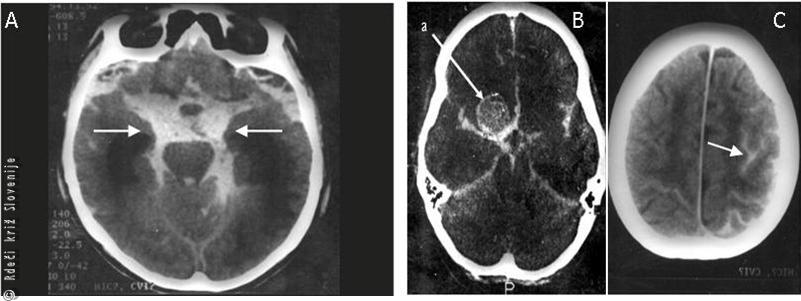

Slika 2

Globinsko slikanje subarahnoidne krvavitve (izliva krvi pod pajčevnico).

A – Obsežna krvavitev, ki takoj privede do izgube zavesti.

B – Obsežna krvavitev in žilna sprememba, ki jo je povzročila (a - anevrizma).

C – Manj obsežna krvavitev, pri kateri je praviloma bolnik pri zavesti, ima pa močan glavobol in otrpel vrat.